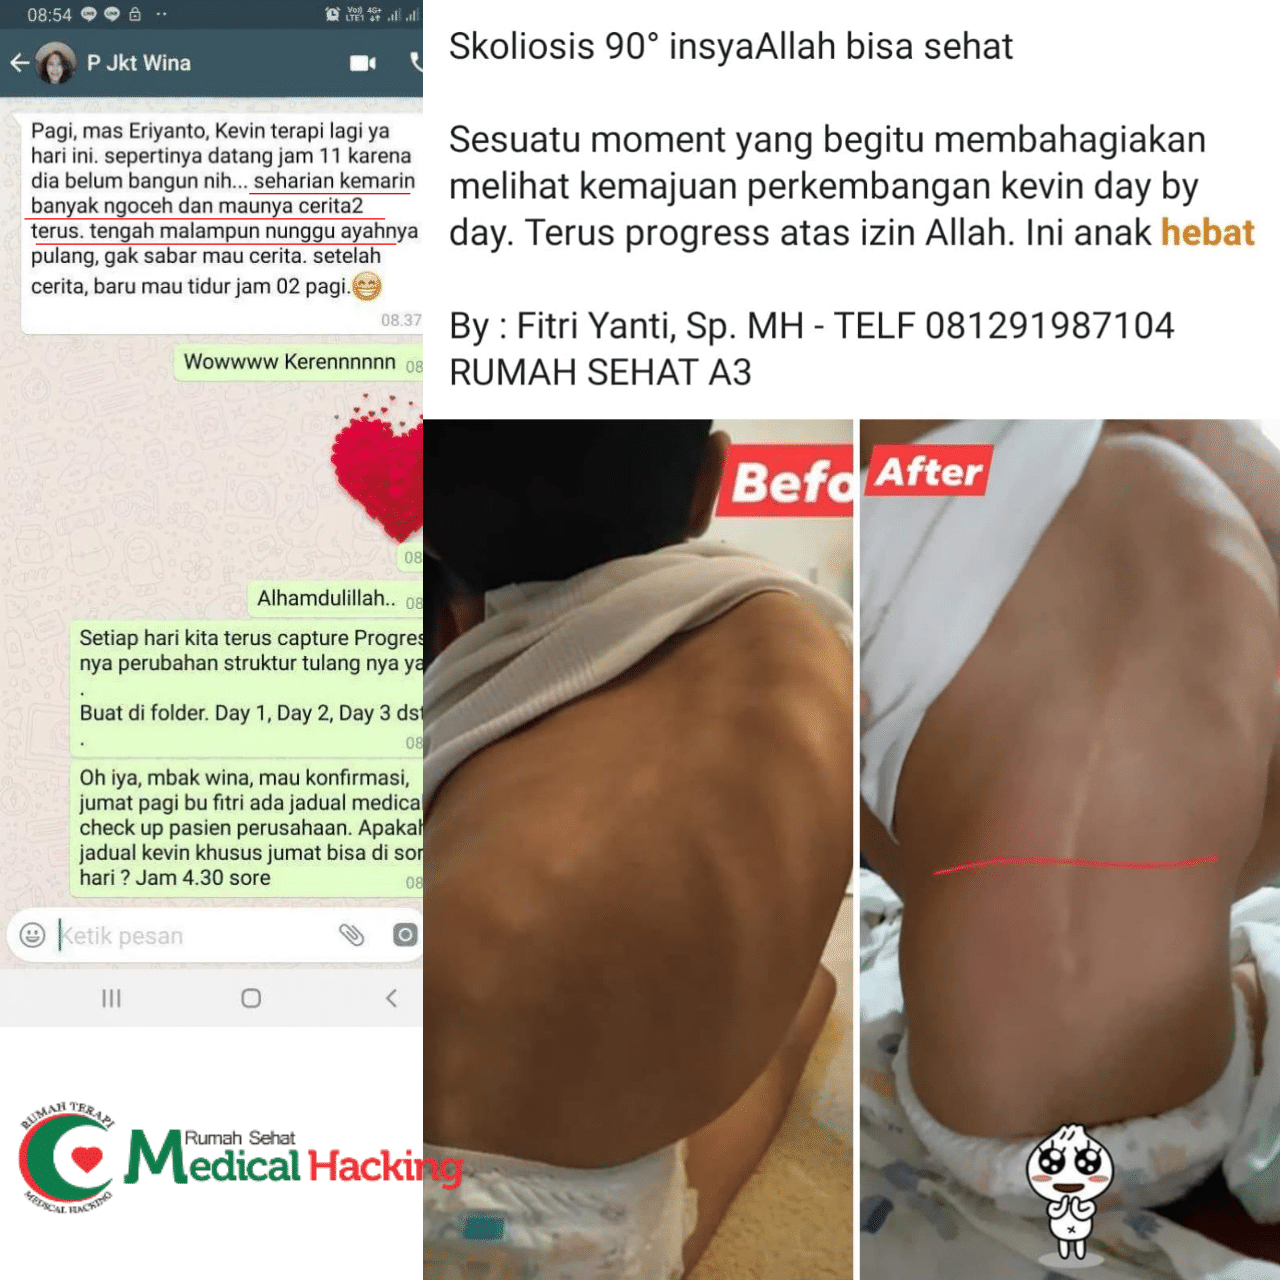

Rumah Terapi Medical Hacking merupakan tempat terapi yang dapat diandalkan untuk mengobati berbagai penyakit secara alami dan menyeluruh, salah satunya adalah radang sendi lutut. Medical Hacking telah dikenal luas sebagai penyedia terapi non-obat kimia yang sudah membantu banyak orang yang kini sudah dinyatakan pulih dari berbagai kondisi medis.

Dengan metode yang mengutamakan keseimbangan tubuh secara alami, Rumah Terapi Medical Hacking telah dipercaya mampu memberikan hasil terapi yang aman dan optimal tanpa efek samping dalam jangka panjang.